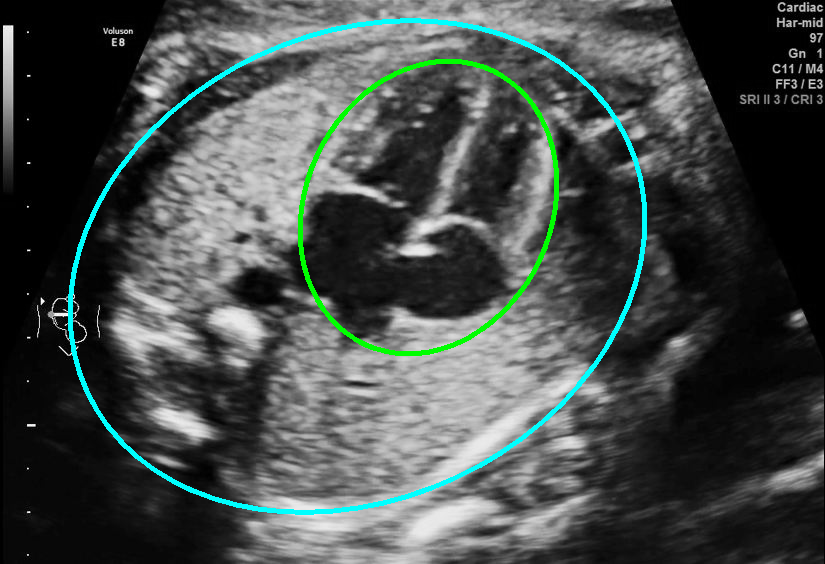

Results of ablation study.

As shown in Fig. 3 , both the proposed ellipse regression loss and IoU loss are necessary for ellipse detection. If the EllipseNet only supervised by IoU loss (first column), the model fails to optimize the major and minor axis separately, and the predicted ellipses degenerate into circles like the CircleNet. It is clear that the supervision of IoU loss can help to improve the prediction of location and shape (first and second row) and to correct the angle (last row).